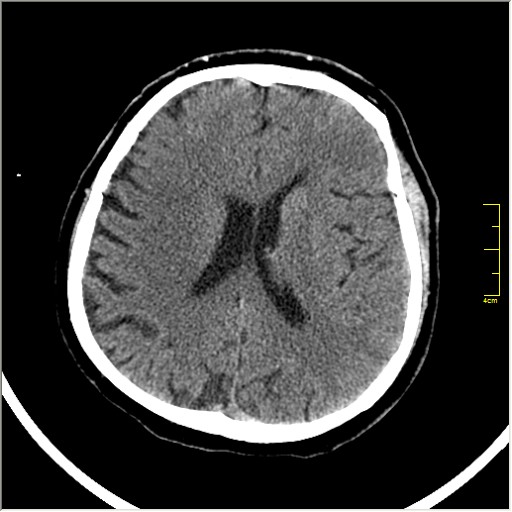

Этот признак называется [Dense MCA sign]; за счёт наличия тромбоза в её просвете. Этот признак является одним из ранних указующих КТ признаков при ишемическом инфаркте головного мозга. Более подробно об этом вы можете прочитать здесь: http://www.radiologyassistant.nl/en/483910a4b6f14.

Ну и для полноты картины, привожу контрольные КТ сканы выполненные через 24 часа: